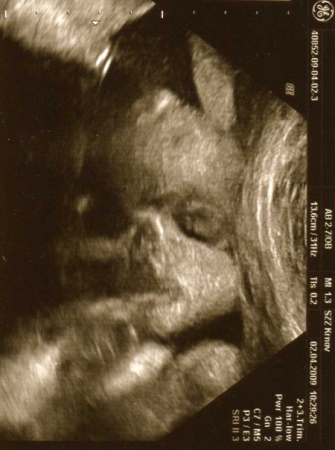

3. Jak vypadá miminko 26. týden těhotenství?

Miminko měří od temene k zadečku 26. týden těhotenství asi 23 cm a váží asi 850 g.